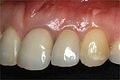

| ■施術前 | ■施術後 | |||

![]() |